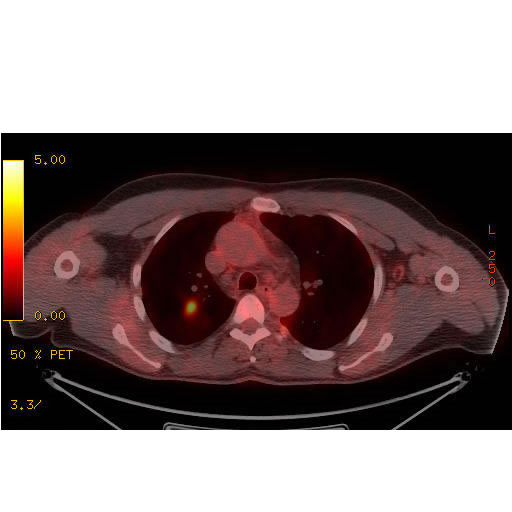

PET scans often inaccurate; may deny curative surgery for lung cancer

The use of positron emission tomography -- better known as PET scans -- has grown dramatically over the past 15 years, thanks to their seemingly magical ability to identify foci of undetected metastatic cancer.

But PET scans' perceived high accuracy in diagnosing metastatic non-small cell lung cancer (NSCLC) -- a published 94% sensitivity and 83% specificity in a 2001 JAMA meta-analysis -- may be vastly overstated, and mask wide geographic variability, according to more recent data. False-positive PET scans may be rampant in Histoplasma-endemic areas, and could result in misdiagnosis of metastatic lung cancer -- with denial of potentially curative resections for stage 1 NSCLC, emerging data suggest.

A 2011 study in Annals of Thoracic Surgery showed that 60% of PET scans suggestive of lung cancer in a Histo-endemic area (Nashville, TN) were false positives. Another 2011 review in the Journal of Thoracic Oncology showed that PET scans can wrongly diagnose locally metastatic disease (N3 lymph nodes) as often as 35% of the time.

Most recently, a post hoc analysis of 682 patients with suspected stage 1 lung cancer who all underwent surgical resection (from a data set presented at the 2012 American Society of Clinical Oncology/ASCO meeting) from dozens of U.S. cities added to the confusion:

Although 82% of the 566 confirmed cancers were PET-avid, 69% of the benign lesions were also PET-avid.

PET's positive predictive value was 85%, but its negative predictive value (likelihood that a negative PET was a true negative) was only 26%.

PET's specificity (avoidance of false positives) was low, and varied widely between cities: it was 46% in Philadelphia (a ~50% false positive rate) but only 15% in Birmingham, AL -- where 85% of the lesions resected were benign (this data suggests).

PET's overall accuracy was 73%, its sensitivity 82%, and its specificity only 31%.

In this series, granulomatous disease was the most common histology found on microscopy of benign lesions.

The National Comprehensive Cancer Network's guidelines recommend the routine use of PET scanning for the diagnosis of non-small cell lung cancer, but this was based on the previously accepted high-performance characteristics. Although no expert body has stepped forward to officially wave the caution flag around PET scanning, it seems evident that false positive PET scans could harm patients through either unnecessary resections or denial of curative resection from falsely positive lymph nodes and/or distant granulomatous disease. Harm from false negatives is also possible, but less likely, given the high sensitivity of PET scanning (although probably not as high as previously believed).